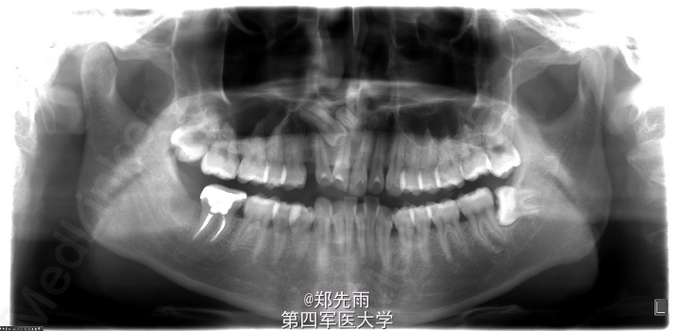

前牙区埋伏牙+上颌窦气化严重

多生牙 埋伏牙 多生牙

正畸要求拔除埋伏牙转诊。 正畸要求拔除上前牙区埋伏13、多生牙以及24、34、44、18、28、38.

13先天性埋伏阻生,前鼻棘下方埋伏牙,行CBCT检查提示均位于唇侧,但CBCT提示双侧上颌后牙牙根不同程度位于上颌窦内。

诊断:13埋伏阻生,上颌埋伏多生牙。 处理:住院拔除上颌埋伏牙,分次拔除正畸减数牙。与患者术前充分沟通上颌窦穿孔、上颌窦瘘的可能。